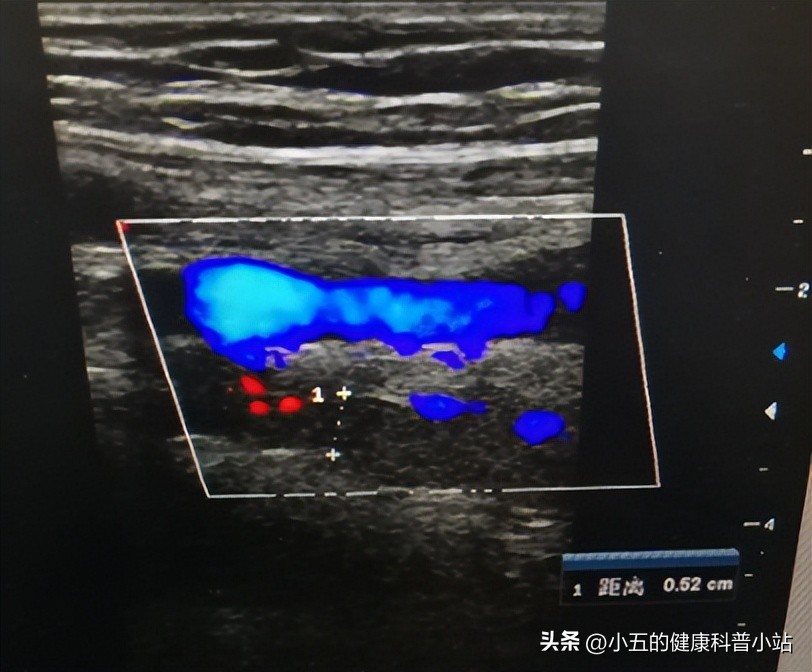

医生听罢孙阿姨的描述后第一时间为其完善了腰椎磁共振和下肢血管彩超,腰椎磁共振虽然可以看到有腰椎间盘突出,但并没有明显的神经压迫,但是下肢血管彩超却发现其下肢动脉有明显的狭窄,结合孙阿姨糖尿病的病史,以及夜间症状明显加重的特点, 医生考虑是不宁腿综合征。

不宁腿综合征是一种排除其他常见病因后的临床诊断 ,在怀疑是不宁腿综合征之前一定要排除腰椎、下肢血管、下肢水肿、关节炎、肌肉痉挛、外伤等多种病因的可能, 因此必须完成相关检查,如腰椎磁共振、下肢血管彩超、下肢肌电图等 。